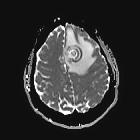

Concentric target sign (cerebral toxoplasmosis)

The concentric target sign is a typical sign for cerebral toxoplasmosis. It is seen on T2 weighted MR imaging as a deep parenchymal lesion showing a series of concentric rings with hyperintense and hypointense/isointense signal alternatingly. Strong perifocal edema is usually visible on T2/FLAIR images.

Histopathologically there are zones of fresh hemorrhage and/or compact coagulative necrosis (hypo/isointense) alternating with zones of edema, fibrin rich necrosis or foamy histiocytic infiltration (hyperintense).